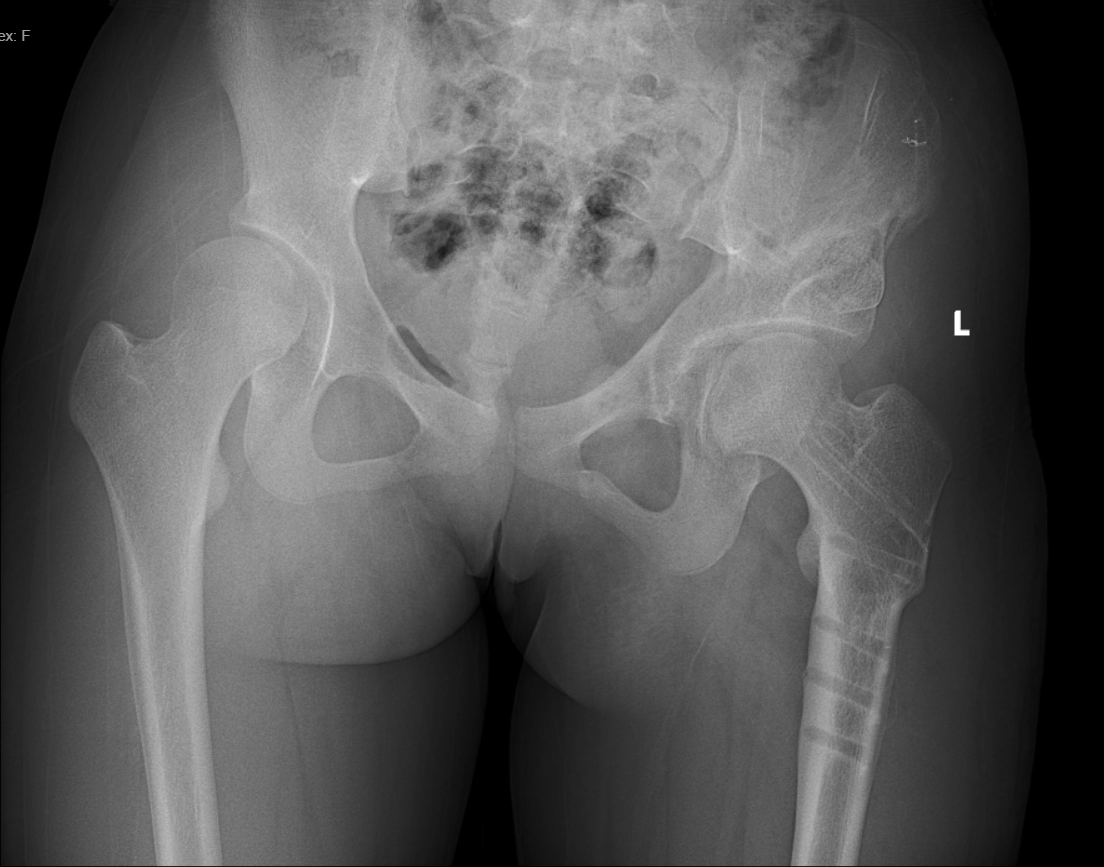

2020-01 术前:双髋关节正位X线片

2020-01 左侧髋臼和股骨近端上下PAO截骨术后第3天:双髋关节正位X线片

2021-07 左侧髋臼和股骨近端上下PAO截骨术后1.5年:双髋关节正位X线片

2021-07 左侧髋臼PAO截骨取钉板术后:双髋关节正位X线片